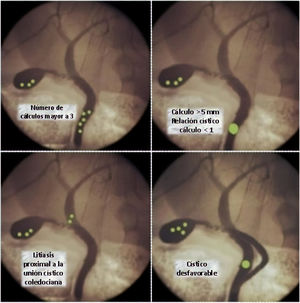

Cuando la inflamación altera la anatomía habitual del triángulo de Calot, o se producen situaciones infrecuentes relacionadas con la coledocolitiasis, la resolución puede acarrear dificultades. Las situaciones desfavorables pueden ser relativas al tamaño, número y ubicación de los cálculos o a variables anatómicas del árbol biliar2–4 (fig. 1).

Ampliación de cisticotomía sobre cálculoCuando la relación cístico/cálculo es<1, es decir que el diámetro del conducto cístico es menor que el cálculo coledociano, el éxito de la instrumentación transcística se ve drásticamente disminuido4.